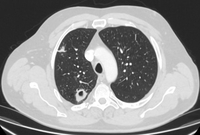

Computed tomography (CT) showing a posterior left upper lobe spiculated nodule, with ‘bronchus sign’ in a female non-smoker. Bronchoscopic forceps biopsy and brushing assisted by radial EBUS miniprobe localisation, confirmed a non-Hodgkin’s lymphoma

From the collection of Dr George Tsaknis, MD, PhD, FRCP(London), MRQA, MAcadMEd, PGCert; used with permission